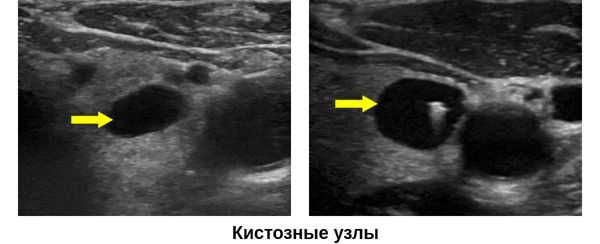

Основным методом диагностики является УЗИ щитовидной железы. На УЗ-картине кисты представлены в виде образований правильной формы с ровными, тонкими стенками и анэхогенным (не отражающим звук), гомогенным содержимым, которые имеют капсулу. Позади кисты присутствует акустический эффект усиления сигнала, что также подтверждает жидкое содержимое кисты.

По данным классификации TIRADS, которая позволяет определить степень риска малигнизации узловых образований щитовидной железы, кистозное строение является благоприятным, т. е. доброкачественным и составляет 0 баллов. [8] Если узел является смешанным (кистозно-солидным), то он соответствует 1 баллу, а если солоидным, то 2 балла.

- Сонографию. При проведении УЗИ щитовидной железы подтверждается наличие образования, определяются его размеры и структура (зоб, аденома, киста щитовидной железы и т. д.).